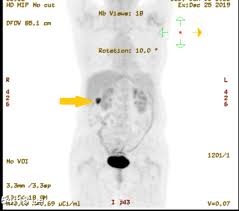

A pet scan can help detect which parts of the heart have been damaged or scarred, and it can help identify circulation problems in the. Pet scans use radioactively tagged molecules (or tracers) to image a wide array of molecular processes and when detected by a pet scanner, the tracers help your doctor to see how well your organs and tissues are working. Nuclear medicine images use a small quantity of a radioactive substance to detect, evaluate, or treat various diseases. Psma pet imaging is a fda approved scan with more precise detection of prostate cancer for better treatment planning and targeted care. These diseases include cancers, heart disease, endocrine, gastrointestinal or neurological.

A pet scan is not specific for cancer. It also can let you and your doctors know if cancer treatment is working. The scanner detects diseased cells that absorb. With that being said, not all cancers can be detected by pet. A pet scan, which uses a small amount of radioactive material, can help show if an enlarged lymph node is cancerous and detect cancer cells throughout the body that may not be seen on a ct scan. Positron emission tomography (pet) imaging scans use a radioactive tracer to check for signs of cancer, heart disease and brain disorders. The pet scan detects the concentrated psma tracer, pinpointing these tumors for more effective treatment. Psma pet imaging is a fda approved scan with more precise detection of prostate cancer for better treatment planning and targeted care. Most pet scans use a type of radiolabeled sugar to detect the cancer, as the majority of cancers grow quickly and need sugar for that growth. Pet can detect extremely small cancerous tumors, subtle changes of the brain and heart, and give doctors important early although cancer spreads silently in the body, pet can inspect all organs of the body for cancer in a single examination. Pet scans, short for positron emission tomography, can detect areas of cancer by obtaining images of the body's cells as they work. Ultrasound is also used to image the abdominal organs and kidneys. To determine whether the cancer has spread.

Pet scans are very useful in detecting diseases like cancer because tumors will be a different color than surrounding tissue activity. Those are detected by pet scanner and a computer converts a signal into detailed images showing how organs are working. The tracer will collect in areas of. Possible risks of a pet scan. The pet scan detects the concentrated psma tracer, pinpointing these tumors for more effective treatment.

Those are detected by pet scanner and a computer converts a signal into detailed images showing how organs are working. Pet is speeding the detection of new drug weapons in the war on cancer. The tracer will collect in areas of. Positron emission tomography (pet) imaging or pet scan is a nuclear medicine imaging. Pet scans use radioactively tagged molecules (or tracers) to image a wide array of molecular processes and when detected by a pet scanner, the tracers help your doctor to see how well your organs and tissues are working. Pet scans are a type of test that create 3 dimensional (3d) pictures of the inside of your body. Pet scan is a special type of imaging test in which tracers are injected & are absorbed into organs of body and images are obtained. For cancer and disease detection, the most commonly used nuclear scan is an fdg pet scan. The pet scanner detects signals that are given off from the tracer. Pet/ct, which is a combination of positron emission tomography (pet) with computerized tomography (ct), is a powerful, essential tool for cancer detection and diagnosis. Diagnosis, cancer staging, treatment diagnosed with cancer and are undergoing active treatment, assess treatment response efficiency and perform cancer monitoring with pet/ct scan! A pet scan is not specific for cancer. With that being said, not all cancers can be detected by pet.